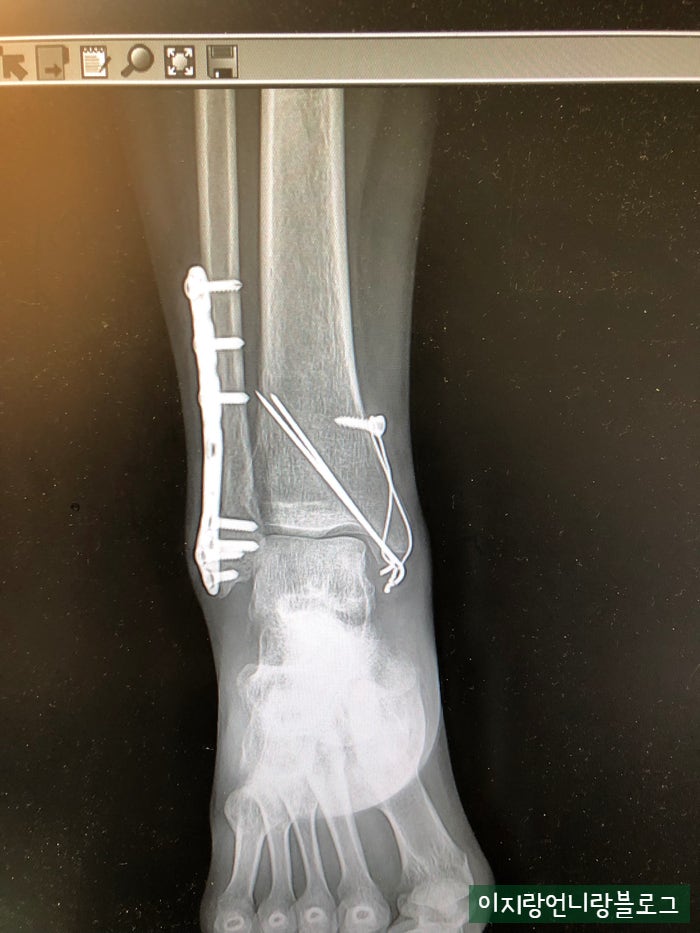

이번에도 무시했던 퇴원비 기다리다가 찾아보니 제일 많이 나오는듯.. 물론 다 이유가 있는듯. 전에. 그는 그것을 확인했다. 이 말을 듣고 또 겁이 나서 사진을 찍었다고 한다. 안전하지 않은 혼합물이 포함되어 있습니다. 이들 중 가장 큰 것은 인공 골분과 같은 것입니다. 의사선생님 말씀에 처음에 넣었다가 동의서에 싸인하고 보니 저렴한 비보험 서비스인줄 알았어요 MRI, 인조골분, 비급여약값 빼면 , 100만 원을 추가로 절약할 수 있었습니다. , 실제 비용 덕분에 정말 운이 좋았습니다. 이번 2건의 수술은 기존에 납부했던 실비를 소진한 것으로 보입니다(참고로 2016년 등록 실비입니다). 또 이번에는 배제가 커서 또 입원 신고가 들어와 모두 접수됐다. 어쨌든 내가 할 수 있고 다리 건강을 유지하는 한 그것은 낭비가 아닙니다. 건강은 무조건 중요하고 중요합니다.

삼각골절정판제거/ 삼각골절정판제거+허리통증 #삼각대골절정술 #삼각대골절정술 #삼트릭스골절정술 #삼트릭스골절정정술 #삼각절단술 … m .blog.naver.com